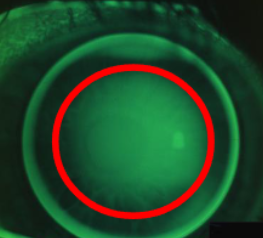

fluorescein pools in the middle but less in the periphery

Bull’s eye pattern

fluorescein patten that can result from a lens that fits too steep

fluorescein pools in center, dark in periphery, edge lift

tear film not exchanged b/t center & outside

becomes uncomfortable or is immediately uncomfortable

lens fits well & holds on over central cornea

top lid fails to pull the steep edge of the lens up

gravity pulls it down

center of gravity of the lens moves farther out in front of the lens the steeper it gets

why does a steep fitting lens usually center or drop?